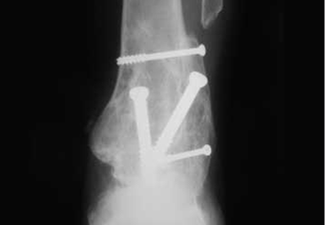

Artrodesis

Uno de los posibles tratamientos quirúrgicos siendo la artrodesis de tobillo. Consiste en la alineación de la deformidad, resección del cartílago y fijación del hueso con distintos tipos de osteosíntesis, lo que dejaba como resultado un tobillo no doloroso, pero rígido.

Se denomina atrodesis a la fijación de la articulación, mediante la resección del cartigalo enfermo y el contacto directo de un hueso con el otro. Generalmente se fija mediante una osteosíntesis con tornillos, placas o fijación externa.

Este es uno de los métodos de tratamiento de la artrosis severa de la articulación del tobillo, y juega con un rol muy importante, ya que nos permite a los cirujanos ortopedistas obtener un pie indoloro, plantigrado y estable.

Puede ser realizada en cualquier situación artrĂ³sica del tobillo, aunque esté asociada a desejes, inestabilidad ligamentaria y desequilibrios musculares.